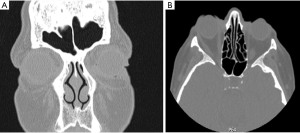

A 75-year-old female patient presented with a one-year history of bilateral nasal congestion and obstruction, which was only partially alleviated by intranasal corticosteroids. No relevant medical or surgical history was reported by the patient. Bilateral hypertrophic ITs (Figure 1A,1B) and septal swell bodies (Figure 1C,1D) were visualized endoscopically. The patient’s computed tomography (CT) scan revealed a relatively straight septum and clear sinuses, in addition to hypertrophic ITs and septal swell bodies (Figure 2A). The lamina papyracea was intact without evidence of dehiscence (Figure 2B). There was an incidental finding of a small retention cyst laterally in the left frontal sinus, as well as mild bilateral proptosis. No intraorbital masses or collections were present. The patient’s Lund-Mackay score was 1/24. To address the patient’s symptoms, coblation of the hypertrophic ITs and septal swell bodies was discussed and consented to (Figure 3).

Although direct orbital infiltration of an anesthetic resulting in oculomotor nerve paralysis was considered, this was deemed unlikely given the intact lamina papyracea (Figure 2B) and the presence of facial paresthesia. We therefore propose three plausible mechanisms to explain the constellation of symptoms observed.